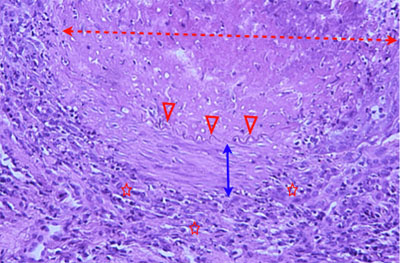

Photo 7 : (Hémalun-Eosine – X200) : vue rapprochée d’une artériole dermique.

L’épaisseur de son intima est irrégulière et anormalement augmentée.

Sa media est hyperplasique. Sa media et son adventice sont infiltrées de cellules inflammatoires.

Légendes de la Photo 7 :

- Étoile turquoise = lumière de l’artériole.

- Flèche double noire = intima de l’artériole.

- Flèche double bleue = media musculaire de l’artériole. Elle est épaissie (hyperplasie musculaire lisse).

- Flèche double turquoise = adventice de l’artériole.

- Pointe de flèche noire = cellule endothéliale – endothélium de l’artériole.

- Pointe de flèche rouge = limitante élastique interne de l’artériole.

- Étoiles rouges = infiltrat inflammatoire dans l’adventice et la media de l’artériole.

- Étoile noire = zone d’épaississement de l’intima et plus particulièrement du tissu conjonctif sous-endothélial de l’artériole.

Photo 8 (Hémalun-Eosine – X400) : vue rapprochée d’une artériole dermique.

Épaississement anormal de son intima. Inflammation de sa media et de son adventice.

Légendes de la Photo 8 :

- Pointe de flèche rouge = limitante élastique interne de l’artériole (serpentin acidophile).

- Étoile noire = zone d’épaississement de l’intima et plus particulièrement du tissu conjonctif sous-endothélial riche en myofibroblastes et en fibres de collagène. L’épaississement aboutit à une réduction de la taille de la lumière vasculaire (artérite oblitérante).